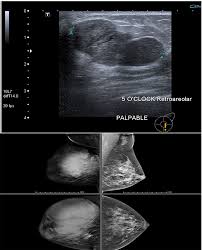

Cellular Fibroepithelial Lesions Diagnosed On Core Needle Biopsy Is There Any Role Of Clinical Sonography Features Helping To Differentiate Fibroadenomas And Phyllodes Tumor Al Arnawoot 2020 Journal Of Surgical Oncology from onlinelibrary.wiley.com The standard treatment for phyllodes tumors is wide excision with sufficient surgical margins. The mainstay of treatment for phyllodes tumors is surgical excision with some debate on the appropriate margin. Macdonald ok, lee cm, tward jd, et al. Surgical margins of >1 cm have been associated with lower local . Malignant transformation with metastases is linked with poor prognosis. If the phyllodes tumor of the breast is benign or borderline histology, radiation therapy not routinely recommended after excision. Phyllodes tumors are rare breast lesions of fibroepithelial origin. All phyllodes tumors, even benign ones, require surgery.

Surgery remains the mainstay of the treatment in patients with malignant phyllodes tumor of the breast (mptb); The mainstay of treatment for phyllodes tumors is surgical excision with some debate on the appropriate margin. If the phyllodes tumor of the breast is benign or borderline histology, radiation therapy not routinely recommended after excision. All phyllodes tumors, even benign ones, require surgery. Because phyllodes tumors mimic fibroadenomas, they are often enucleated or excised with a close margin. In the setting of malignant . Malignant transformation with metastases is linked with poor prognosis. An exceptional response to therapy in a malignant phyllodes tumor. The standard treatment for phyllodes tumors is wide excision with sufficient surgical margins. If the tumor has malignant . You only have chemotherapy if the phyllodes tumour is cancerous, and has spread to another part of the body. Tumor genomic analysis using the trusight oncology 500 assay . Phyllodes tumors are rare breast lesions of fibroepithelial origin.

Because phyllodes tumors mimic fibroadenomas, they are often enucleated or excised with a close margin. Phyllodes tumors are rare breast lesions of fibroepithelial origin. An exceptional response to therapy in a malignant phyllodes tumor. The standard treatment for phyllodes tumors is wide excision with sufficient surgical margins. Tumor genomic analysis using the trusight oncology 500 assay .

Surgical margins of >1 cm have been associated with lower local . Surgery remains the mainstay of the treatment in patients with malignant phyllodes tumor of the breast (mptb); Macdonald ok, lee cm, tward jd, et al. In the setting of malignant . If your tumor is malignant, you may need more aggressive surgery and other treatment. You only have chemotherapy if the phyllodes tumour is cancerous, and has spread to another part of the body. Malignant phyllodes tumor of the female breast: The standard treatment for phyllodes tumors is wide excision with sufficient surgical margins. All phyllodes tumors, even benign ones, require surgery. An exceptional response to therapy in a malignant phyllodes tumor. Tumor genomic analysis using the trusight oncology 500 assay . Because phyllodes tumors mimic fibroadenomas, they are often enucleated or excised with a close margin. Phyllodes tumors are rare breast lesions of fibroepithelial origin.